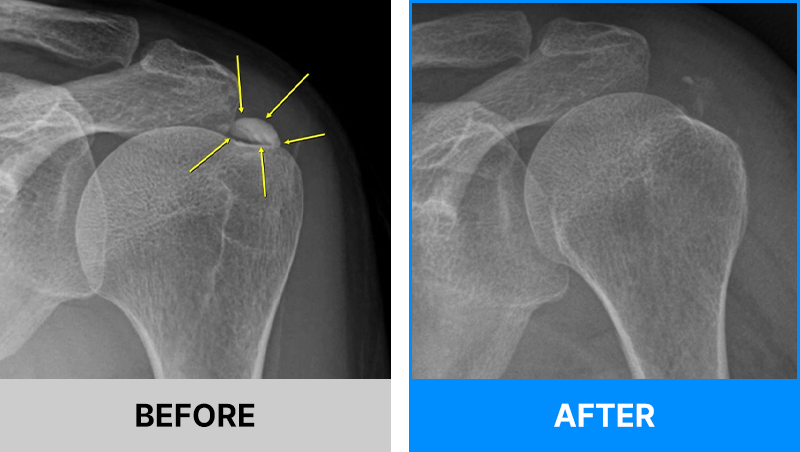

어깨의 석회는 그 시기에 따라 액체형과 고체형 그리고 혼합형으로 존재할 수 있습니다.

액체형 석회를 흡인하는 것은 어디에서나 가능합니다. 하지만 고체형 그리고 혼합형 제거에는 많은 노하우가 필요합니다.

서울거탑정형외과에서는 고체형 석회를 잘게 분쇄하여 뽑아내는 독자적인 기술과 노하우를 보유하고 있습니다.

형성기/휴지기의 고체형 석회

흡수기의 액체형 석회

해당 시술은 석회의 위치를 초음파로 정확히 확인한 뒤,정교한 기술로 진행되는 비수술 치료입니다.

그만큼 의료진의 숙련도와 경험이 매우 중요하므로, 풍부한 시술 경험을 가진 정형외과 전문의를 통해 치료받는 것이 좋습니다.

서울거탑정형외과에서는 풍부한 노하우로 초음파를 통해 정확히 석회를 확인 후 고체형일지라도 미세하게 분쇄하여 제거가 가능합니다.

95%이상 석회 제거가 가능합니다.

급성 흡수기 석회의 경우 시술 직후부터 통증의 완화가 매우 뚜렷합니다.

하지만 형성기 석회의 경우 시술 후 수 일 ~ 2주 정도는 통증이 조금 있을 수 있고 그 뒤부턴 일반적으로

통증 호전을 경험하시며 3개월 전후까지 꾸준히 좋아지는 것을 느끼실 수 있습니다.